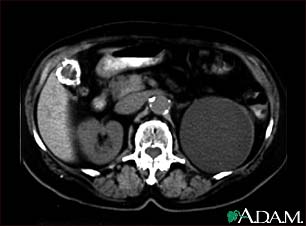

Kidney cyst with gallstones, CT scan

A CT scan of the upper abdomen showing a fist-sized cyst of the left kidney and gallstones (the kidney cyst was found by chance; there were no symptoms).